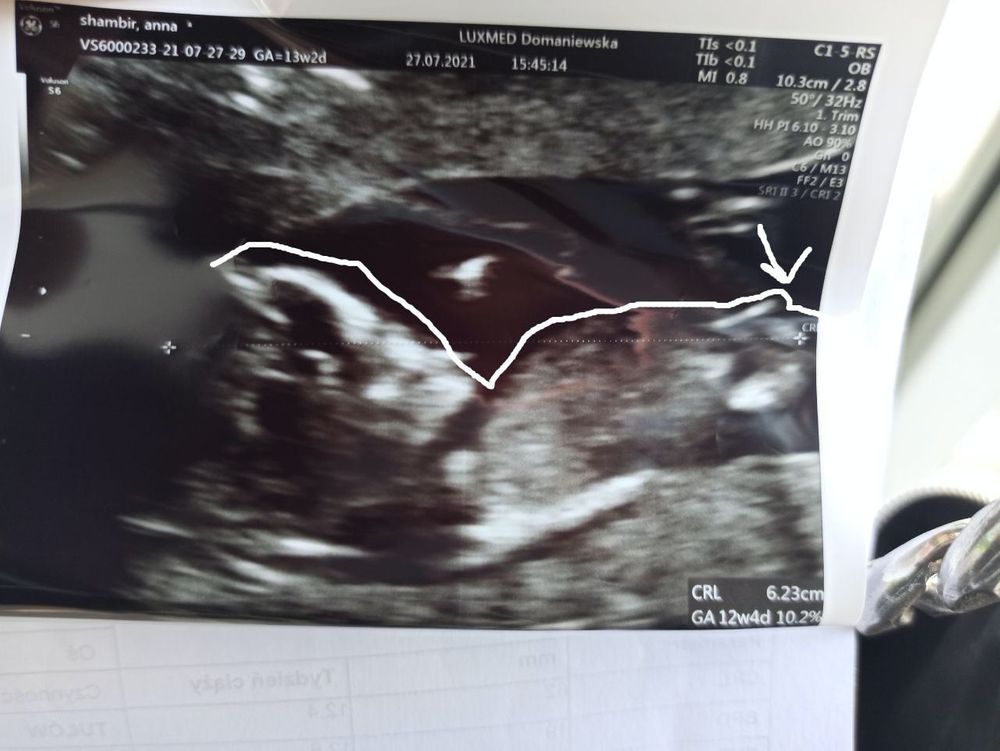

Вот только то, о чем так волновалась - пол - так сегодня и не узнала, но пока смотрела, теперь уверенна, что девочка (насмотрелась видео о том, как выглядит половой бугорок на этом сроке). Паралельно позвоночнику - значит девочка. А у вас как было? 🥰

Мария, да, видела, перед этим насмотрелась много видео как определять. Я была настроена на мальчика все время, сны снились с сыном, но там мальчиком и не пахнет. Посмотрите мой коммент с фото :)

Ani S, Ну если это точно половой бугорок на фото, то похоже) Просто фото немного неудачное, он как-будто не совсем в кадре и детализация не такая как хотелось бы. У меня на скрининге прям все четко видно было, если бы было по качеству как у вас, то даже не предполагала бы кто))

Мальчиком там и не пахнет :)

Ani S,